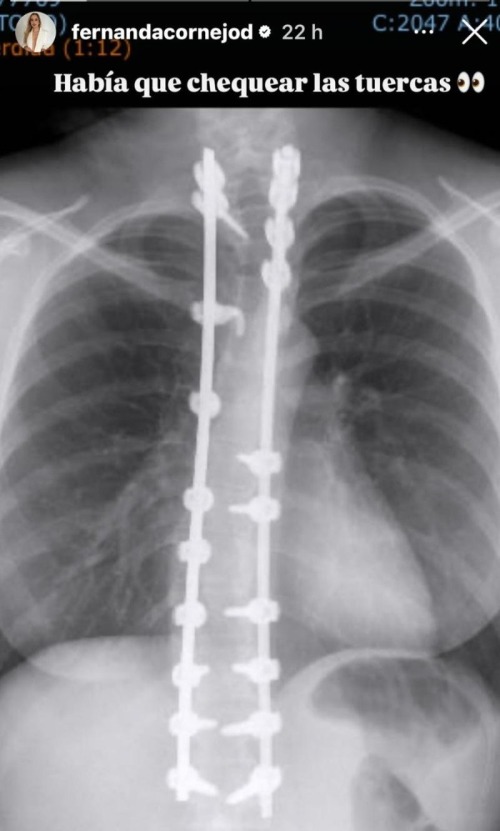

Se trata de una radiografía en la que aparece su columna y en la que se logra apreciar varias placas de titanio "sosteniéndola", las que a su vez están siendo afirmadas por decenas de pernos distribuidos en la espalda.

“Había que chequear las tuercas”, escribió con humor la cientista política que hoy trabaja en el canal de televisión C5N de Argentina, en referencia a la operación por su escoliosis idiopática.

“Yo tengo cuatro prótesis de titanio y tengo alrededor de 68 pernos en la espalda, fue una operación grave, grave”, recordó en el programa, junto con asegurar que la desviación de su columna estuvo "al borde de que me perforara un pulmón".